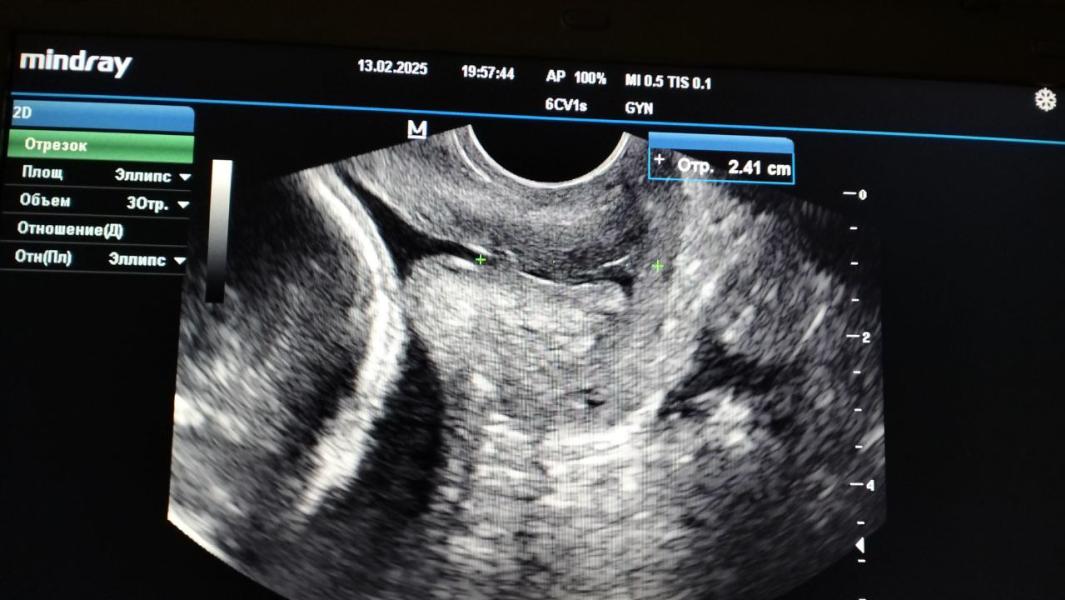

На 21 неделе я узнала, что у меня умерла крестная, а через пару дней на плановом осмотре гинеколог увидела воронку у шейки и укорочение. Это был вечер четверга, мы поехали домой, собрали вещи и прямиком в перинатальный центр. Меня положили в патологию, планировали накладывать серкляж. Самое грустное, что в ту злополучную пятницу был день открытых дверей. И если вечером в четверг шейка была еще 24 мм, то утром в пятницу она была уже 16мм. Но как бы я не уговаривала врача, она сказала, что шить будут только в понедельник. Потому что без заведующей она не может ничего сделать, а заведующая проводит экскурсию, поэтому лежи, задрав ноги.